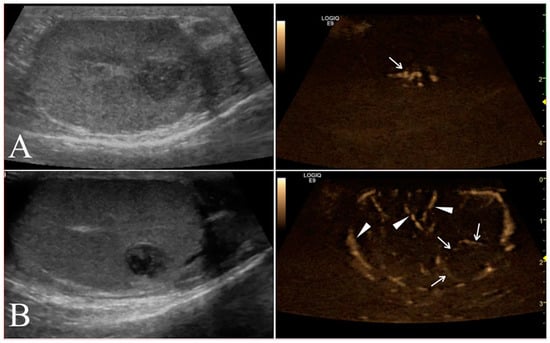

Longitudinal and transverse views were obtained from each testis using B-mode. B-Mode ultrasound parameters included anatomical site of affected testicle (scrotal or abdominal), maximal diameter (cm), location (left, right, or both testicle), margins (regular, irregular), echogenicity (hyperechoic, hypoechoic, isoechoic, anechoic or mixed), and echotexture (homogeneous or inhomogeneous) of the lesions relative to normal surrounding (or contralateral, in the case of a diffuse lesion) testicular parenchyma (Figure 1).

Figure 1. Representative B-Mode ultrasonography scans. (A) Left testis of a 11 year old mixed breed dog with a focal hyperechoic nodule (seminoma) characterized by homogenous echotexture and regular margin. (B) Mixed cell tumor (leydig and seminoma) recorded as two nodular lesions in the right testis of a 13 year old Epagneul Breton. The lesions had mixed patterns, inhomogeneous echotextures and irregular margins.